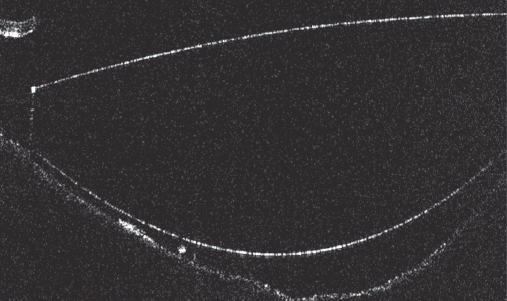

In all eyes, on day 1 and day 7 after PE, the IOL–PC interface was examined on the RS3000 Advance device (Nidek, Japan) to assess the IOL contact with the capsule (Figs. 1–3).

Fig. 2. Incomplete contact between IOL and posterior lens capsule / Рис. 2. Частичный контакт интраокулярной линзы с задней капсулой хрусталика